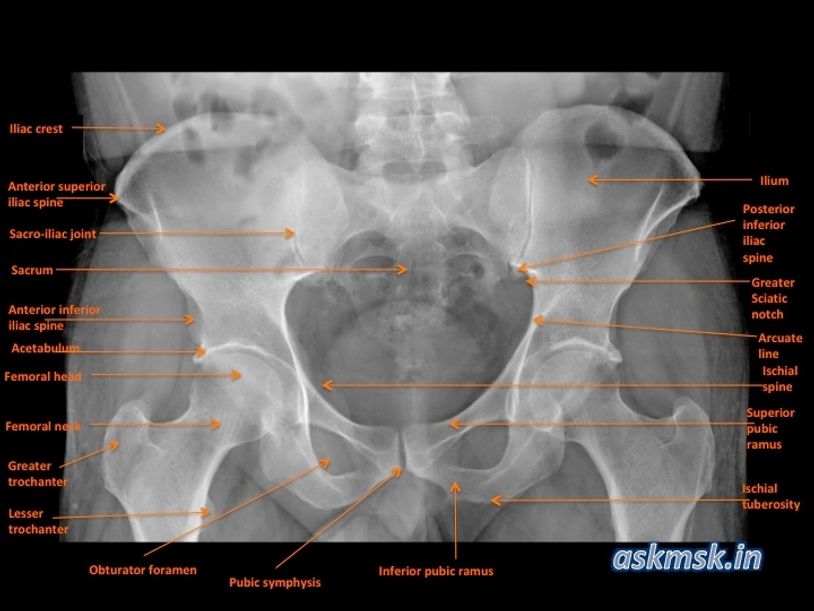

Labeled Pelvis Xray . Assess relationship of femoral head + acetabulum. pelvis tilted anteriorly 45° + hips abducted. Your pelvic bones include your hip bones (ilium, ischium. in the figures that follow, a number of frequently encountered fracture patterns are described and illustrated. the ap pelvis view is part of a pelvic series examining the iliac crest, sacrum, proximal femur, pubis, ischium and the great pelvic ring.